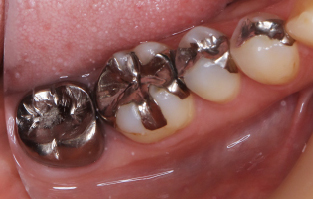

- 32 メタルインレー除去、ハイブリッドセラミックインレー形成印象の症例

| 主訴 | 銀歯を白くしたい |

| 治療内容 | 金属除去、つめ物かぶせ物治療 |

| 治療期間 | 2週間 |

| 治療費用 | 総額 330,000円(税込) つめ物(セラミックインレー) 55,000円(税込) ×2 かぶせ物(ジルコニアステインクラウン) 110,000円(税込) ×2 |

| 副作用等 | 神経の治療 |

| 治療方針 | 金属を除去し中の虫歯を しっかりとりきりセラミックのつめ物 |

| 特記事項 | 金属の中は虫歯になっており、 症状がなかったが神経まで達していて 神経の治療が必要になったケースです。 |

| 担当者所見 | 一本ずつではなく同時にブロックで型取り、 色味合わせを行なったため精度、 審美面どちらも患者さまには満足していただけました。 |